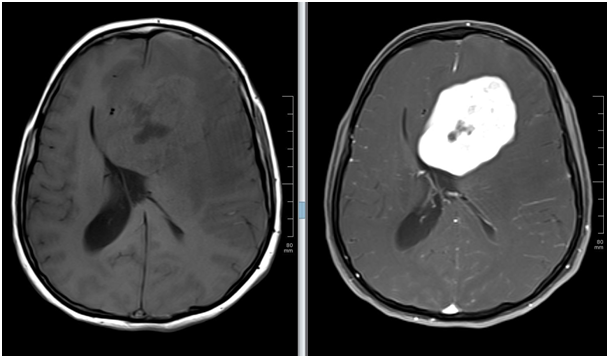

Conventional MRI

Methods are superior too the resectional imaging methods for these evaluations. In conventional MRI, sections through the brain are obtained. These images show location, and relationship of them as slesions. IV contrast materials which contains Gadolinium (Gd) is also frequently used to define vascularity and enhancement patterns of the tumors. Enhancement patterns may also used to predict tumoral grade. Low grade (grade 1 & 2) tumors usually do not show contrast enhancement, where as high grade (grade 3 & 4) tumors show prominent enhancement (Figure 1). Sensitivity of the presurgical estimation of tumor grade can be increased by using advanced neuroimaging techniques. As well some of these techniques can also be used to evaluate infiltration of the eloquent areas. These advanced techniques include diffusion-weighted imaging (DWI), diffusion tract imaging (DTI), perfusion-weighted imaging (PWI), and MR-spectroscopy (MRS).

Figure 1 Glioblastome multiforme. Left frontal mass showing intense contrast enhancement and mass effect.